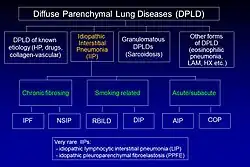

Classificação

A fibrose pulmonar idiopática (FPI) pertence a um grande grupo de mais de 200 doenças pulmonares conhecidas como doenças pulmonares intersticiais (DPIs), que são caracterizadas pelo envolvimento do interstício pulmonar,[9] o tecido entre os sacos aéreos do pulmão. A FPI é uma apresentação específica da pneumonia intersticial idiopática (PII), que, por sua vez, é um tipo de DPI, também conhecida como doença pulmonar parenquimatosa difusa.

A classificação das PIIs da ATS e ERS de 2002 foi atualizada em 2013.[9] Nessa nova classificação, há três categorias principais de pneumonias intersticiais idiopáticas (PIIs): PIIs principais, PIIs raras e PIIs não classificáveis. As principais PIIs são agrupadas em PIIs fibrosantes crônicas (incluindo FPI e pneumonia intersticial não específica [PINE]); PIIs relacionadas ao tabagismo (ou seja, bronquiolite respiratória - doença pulmonar intersticial [BR-DPI] e pneumonia intersticial descamativa [PID]); e PIIs agudas/subagudas (ou seja, pneumonia organizativa criptogênica [COP] e pneumonia intersticial aguda [PIA]).[9]

O diagnóstico de PIIs requer a exclusão de causas conhecidas de DPI. Exemplos de DPI de causa conhecida incluem pneumonite por hipersensibilidade, histiocitose pulmonar de células de Langerhan, asbestose e doença vascular do colágeno. No entanto, esses distúrbios frequentemente afetam não apenas o interstício, mas também os espaços aéreos, as vias aéreas periféricas e os vasos sanguíneos.[9]